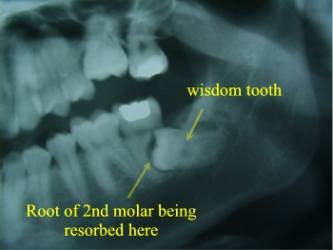

Wisdom Tooth Resorbing 2nd Molar

Impacted Wisdom Tooth Causing Cavity and Bone Loss at the Back of the 2nd Molar

Alternatively, the other question you should ask yourself is ‘What are the risks of not doing surgery and leaving the wisdom teeth behind? When the wisdom teeth erupt through the gums completely, and are able to reach the proper, healthy position in the jawbone, there is little risk in keeping them or ‘not doing surgery’. These properly positioned wisdom teeth are only slightly more likely to develop cavities or gum disease as compared to the other back-teeth in your mouth. However, when a wisdom tooth is impacted or malpositioned, the tooth and associated gum can be very susceptible to bacterial infection, localized gum disease, and gum abscesses. These problems sometimes occur with very little associated pain or discomfort. In such cases, the gum disease and/or infection will progress ‘silently’ until the tooth in front of the wisdom tooth, along with its supporting gum and bone tissue, is damaged. (see figures 2 and 3)